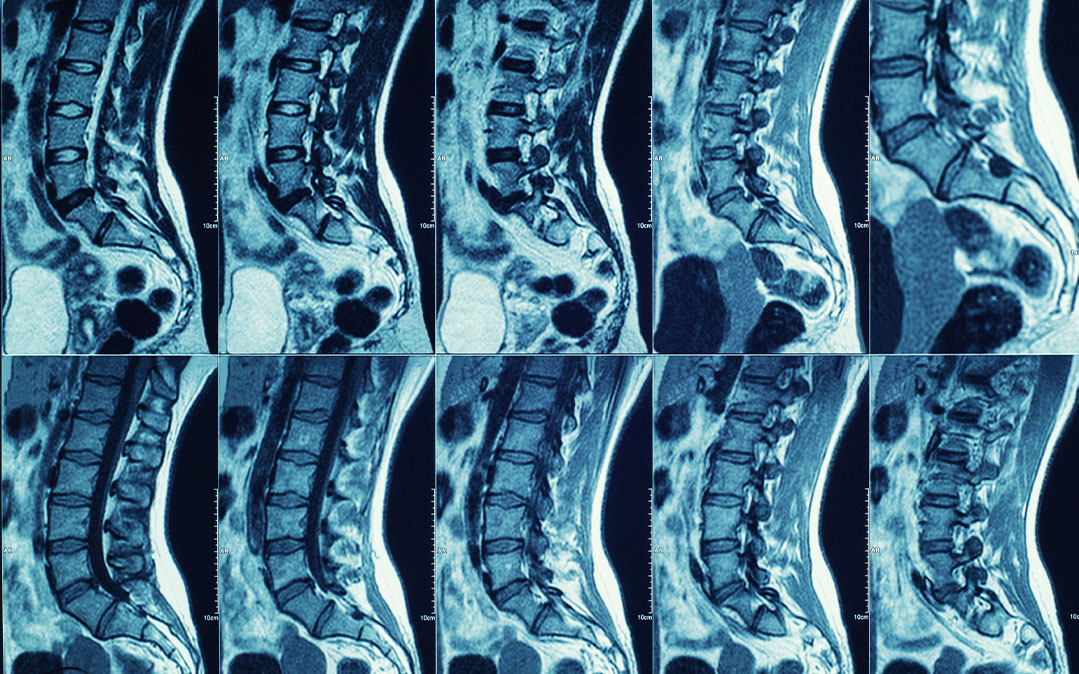

A Ressonância Magnética é um dos exames de Imagiologia com maior precisão. Permite obter imagens de elevada resolução, grande detalhe e é uma ferramenta essencial para revelar aquilo que outros exames não conseguem com um nível tão elevado de clareza.

Ao contrário de outros exames radiológicos, como o Raio-X ou a Tomografia Computadorizada (TC/TAC), a Ressonância Magnética não produz qualquer tipo de radiação ionizante. O aparelho de Ressonância Magnética é composto por um íman muito forte, que se encontra dentro do cilindro do equipamento. As imagens são criadas através da utilização de pulsos de radiofrequência, que estimulam os átomos de hidrogénio presentes no corpo humano. Quando os átomos de hidrogénio voltam à sua posição original, é captado o sinal que cria as imagens extremamente detalhadas do interior do corpo humano.

Uma Ressonância Magnética pode demorar entre 20 a 90 minutos, dependendo da região anatómica (área do corpo) a analisar. Ao longo do exame são executadas várias sequências de imagens de elevada resolução e precisão, com o objetivo de analisar diferentes tipos de tecidos. Cada sequência pode demorar, em média, entre 1 e 9 minutos. Se uma imagem ficar “tremida”, a sequência terá de ser repetida, o que aumenta o tempo de realização do exame. É por isto que é tão importante o paciente manter-se sem se mexer ao longo do exame e o mais imóvel possível, uma vez que a sensibilidade do equipamento a qualquer tipo de movimento durante a aquisição de imagem é bastante elevada.

O equipamento de Ressonância Magnética da Cintramédica é o aparelho VantageElan, da marca Canon Medical, capaz de obter imagens de grande qualidade. O seu formato é em túnel ou cilindro, fechado lateralmente e aberto nas extremidades. Em alguns exames, como é por exemplo o caso dos joelhos, pés e tornozelo, a zona da cabeça não entra dentro do equipamento.